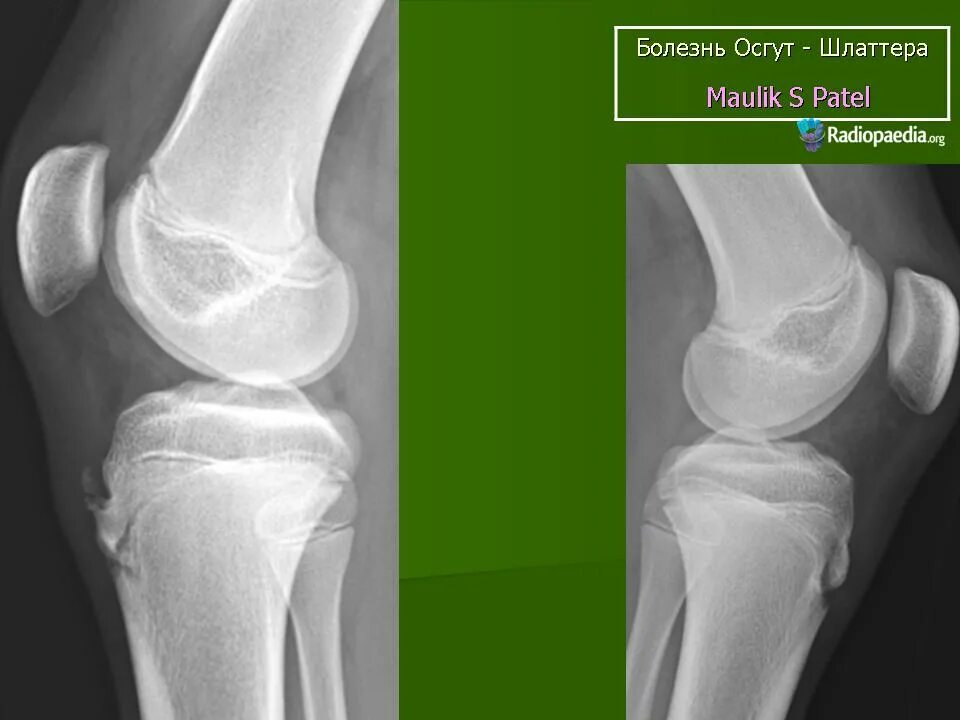

Болезнь осгут шляттера